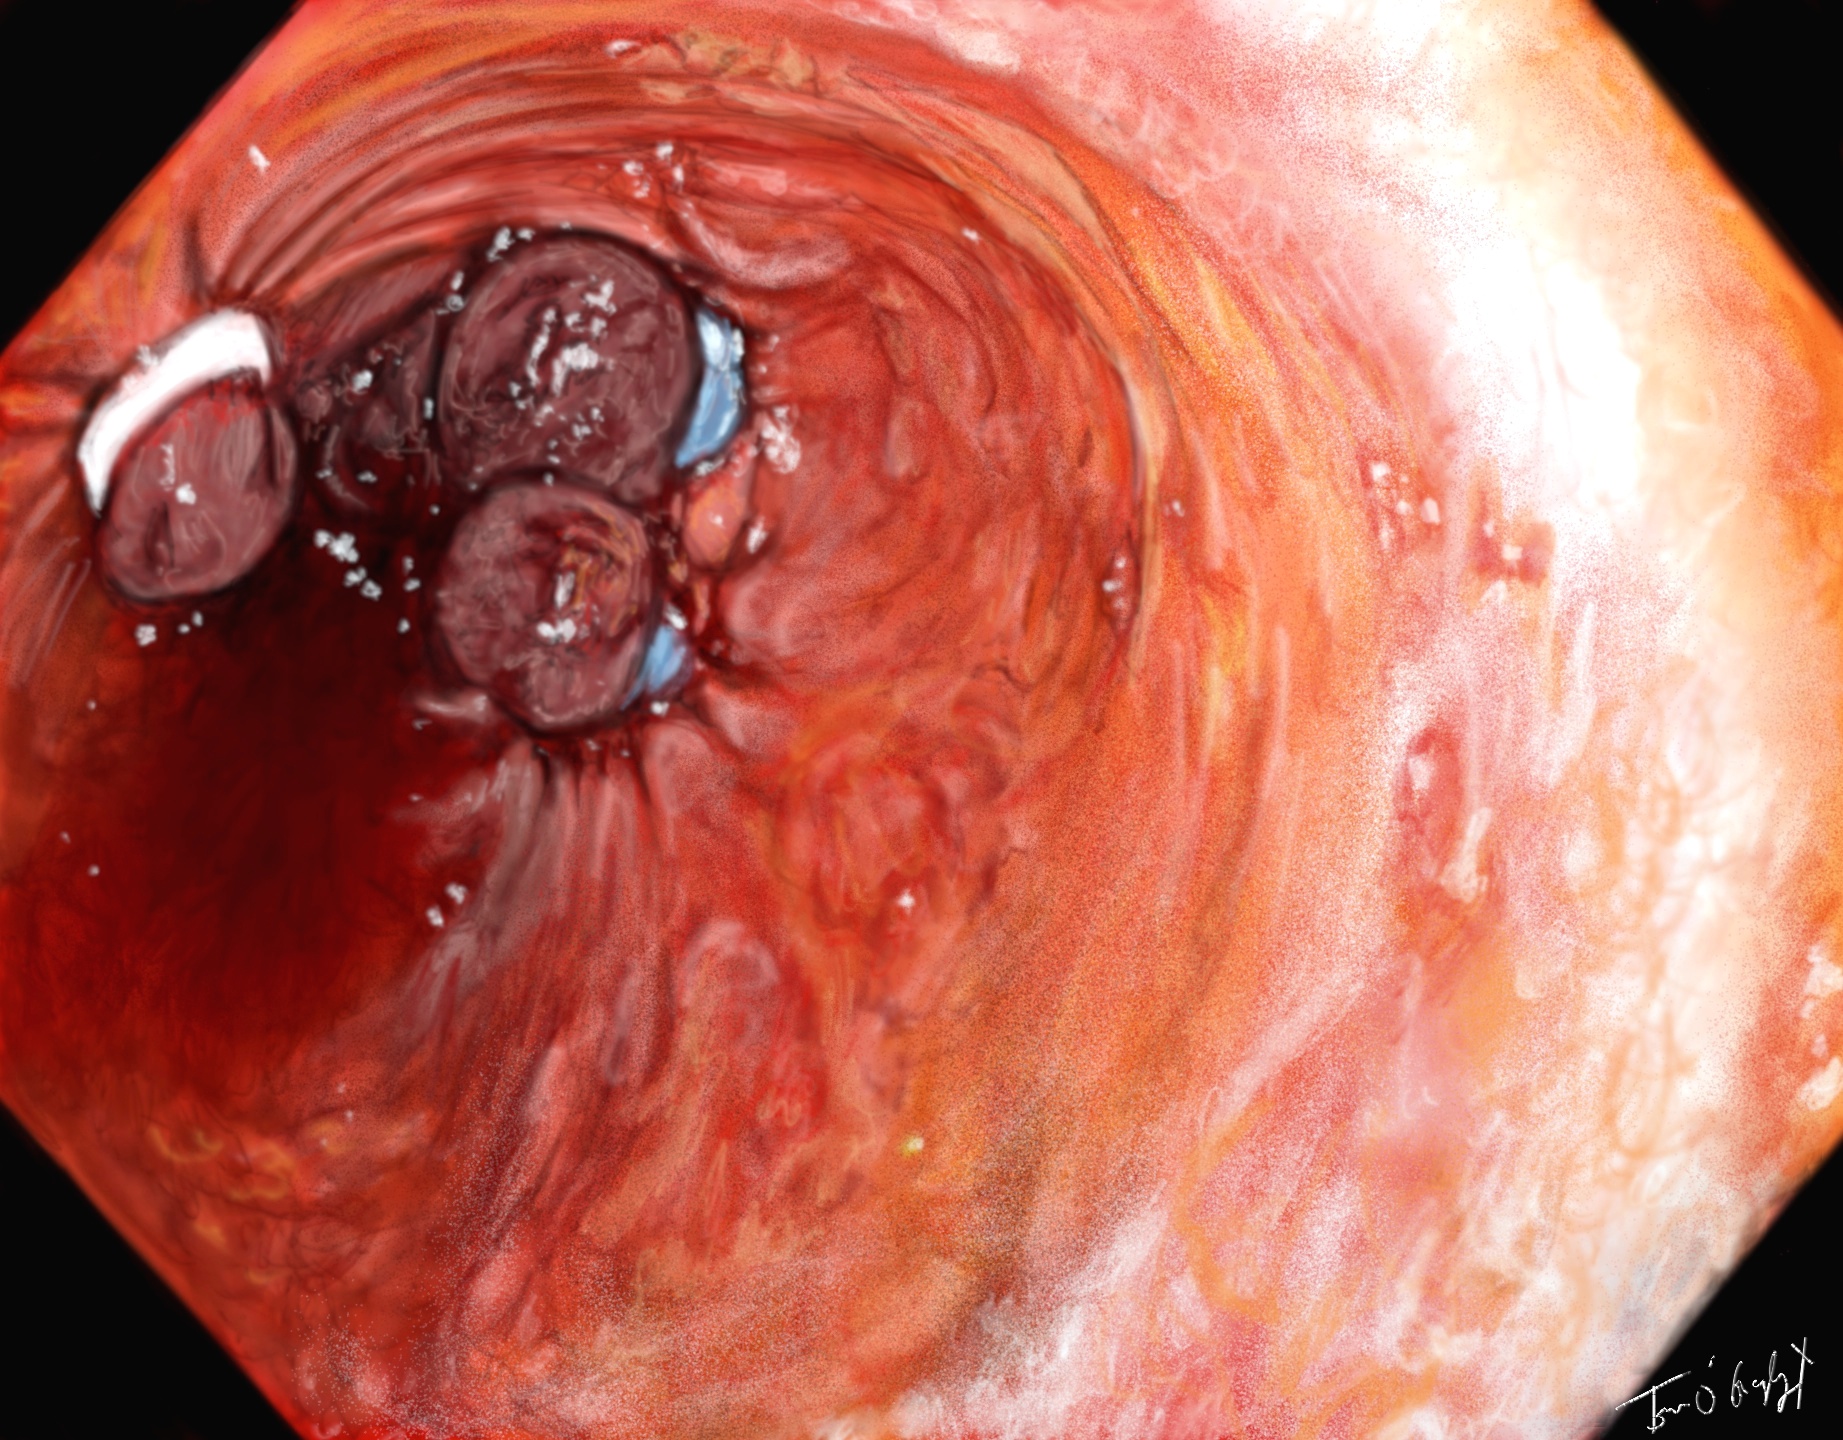

Ligature de varices oesophagiennes en endoscopie

Dans tous les cas le traitement définitif est réalisé sous endoscopie, avec injection locale d’adrénaline, ligature élastique des varices oesophagiennes, thermocoagulation, compression mécanique (stent ?) des ulcères gastriques et VO.

Rupture de varices oesophagiennes

La baisse du débit splanchnique obtenu par ces vasopresseurs sera relayé au bout de 5 jours par les bêta-bloquants. En cas d’échec de l’endoscopie, un shunt porto-cave TIPS peut être réalisé ou dans les 72h en prévision de la récidive chez les patients à haut risque. En attendant ce shunt porto-systémique, une sonde de tamponnement oesophagien doit être mise en place pour une durée ≦ 24h, gonflée à l’air, exposant au risque d’ischémie oesophagienne. Au décours de l’évènement, une antibiothérapie probabiliste préventive par fluoroquinolones : norfloxacine 400 mg × 2/j ou céphalosporine de 3ème génération, pendant 7 jours est indiquée chez le cirrhotique, de même que l’utilisation de lactulose pou prévenir l’encéphalopathie. Chez les coronariens et malades sous antiagrégants plaquettaires en association, seule l’aspirine doit être maintenue en attente de l’avis cardiologique.